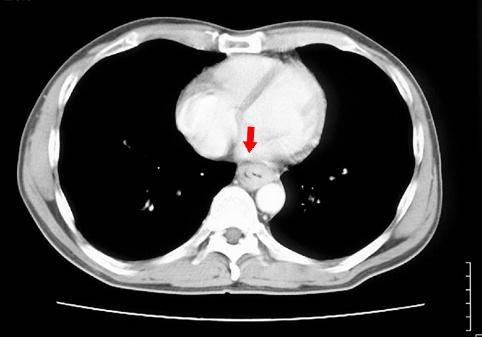

疾病(病理主体)的分类恶性上皮肿瘤/扁平上皮癌

部位(按器官分)食道/下

检查方法CT

肿瘤的肉眼分类3型(溃疡浸润型)/

肿瘤最大直径40以上

肿瘤的深度s(a)